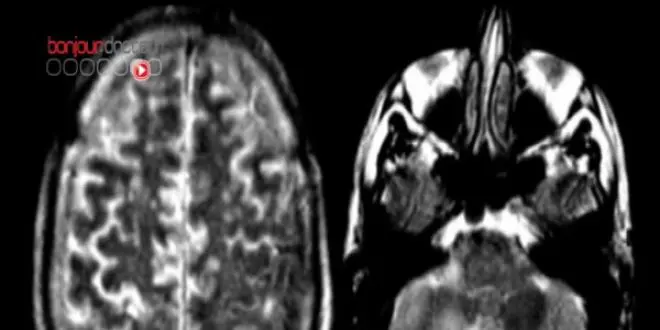

Il s'est avéré que ces difficultés de mémorisation induites par les glucocorticïdes s'accompagnaient d'une réorganisation de l’activité du cerveau, et en particulier du circuit hippocampe-amygdale, qui stocke les souvenirs liés à la peur.

Dans les conditions normales, quand une personne associe une menace à un contexte, on observe une forte activité dans l’hippocampe, la structure du cerveau nécessaire pour tous les apprentissages qui associent un contexte particulier. En revanche l’activité de l’amygdale est faible. L’amygdale est une zone du cerveau aussi impliquée dans la mémoire émotionnelle, mais elle mémorise les indices spécifiques, comme des sons, qui prédisent la menace.

Quand les sujets sont soumis à une augmentation des glucocorticoïdes et que des déficits de mémoire qui caractérisent l'ESPT sont observés, l'activité normale de ces deux zones s'inversent... L'activité anormale dans l'amygdale pourrait expliquer le fait que les personnes commencent à "sur-répondre" à des éléments anodins. Quant à l'activité faible dans l'hippocampe, elle pourrait expliquer que ces personnes ne reconnaissent plus le bon contexte et soit donc incapable de confiner la réaction de peur à la situation appropriée.